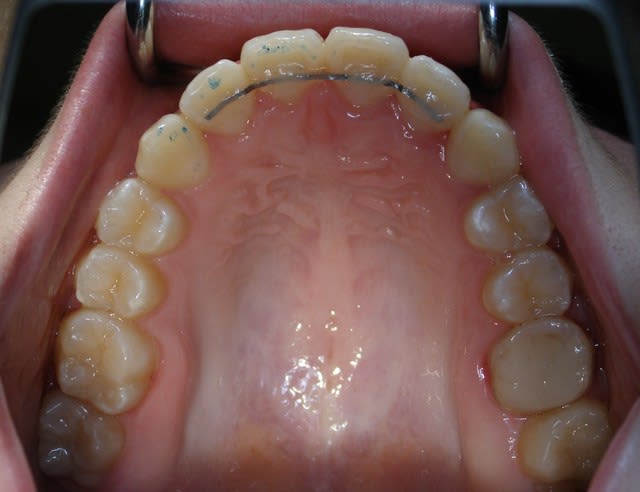

Ma contention...fil plat tréssé 8 brins...33€ les 10 brins de 10 cm... pas cher donc et taux de satisfaction "perso" de 99,99%. Du faite du plat du fil, la couche de composite peut-être réduite au minimum.

J'ai eu aussi la période gouttière..positionneur...plaque...3-3 préfabriqués...mais c'est le fil qui reste le plus fiable (compromis maintien/souplesse ) et le moins contraignant à gérer.

Au maxillaire, le plus possible de 2 à 2; sinon hawley classique.